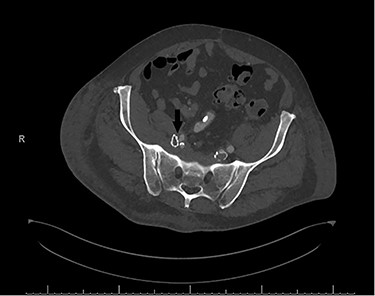

In the immediate postoperative period, the patient was found to have weakness of the right foot, which was cool and pulseless. A computerized tomography angiogram showed well-positioned venous stents, but the right EIA was occluded from its origin to 4–5 cm distally (Fig. 2).

Postoperative computerized tomography angiogram with an arrow demonstrating likely point of compression of left EIA by venous stent.